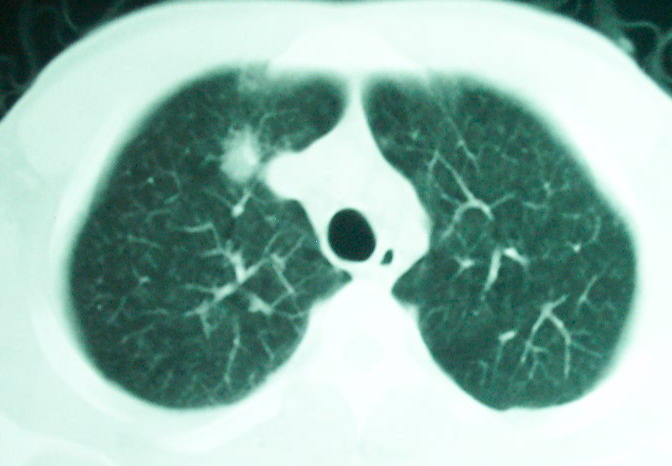

m      37y      发热   咳脓痰月余      ct肺脓肿但住院抗炎治疗后双肺内结节不知该如何解释

治疗后见左肺下野病灶较前缩小但双肺内结节影似无变化请较各位老师该如何下结论    治疗前wbc14.5 治疗后wbc 11.0

我看是不是可以两元化来解释,左肺下叶还是肺脓疡,而其余病灶考虑肺癌伴肺内转移,我看右肺上叶尖段病灶可见明显毛刺改变为原发病灶.

左下肺病灶除了明显的厚壁空洞 气液平外,明显见壁结节,另两肺多发小结节,综合考虑:左下肺周围性肺癌伴肺内转移.

如果你仔细的同层面对比,你会发现所有的病灶均有比较明显的吸收、缩小。病变的形态,特别是脓肿的形态、壁的厚薄、内壁均有很大的变化,均在往好的方面发展。与临床症状、血像均符合,治疗效果比较显著,就是肺脓肿并双肺的化脓性炎症灶。